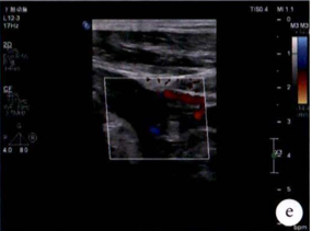

图:e)术前评估时腘动脉未见血流图像;